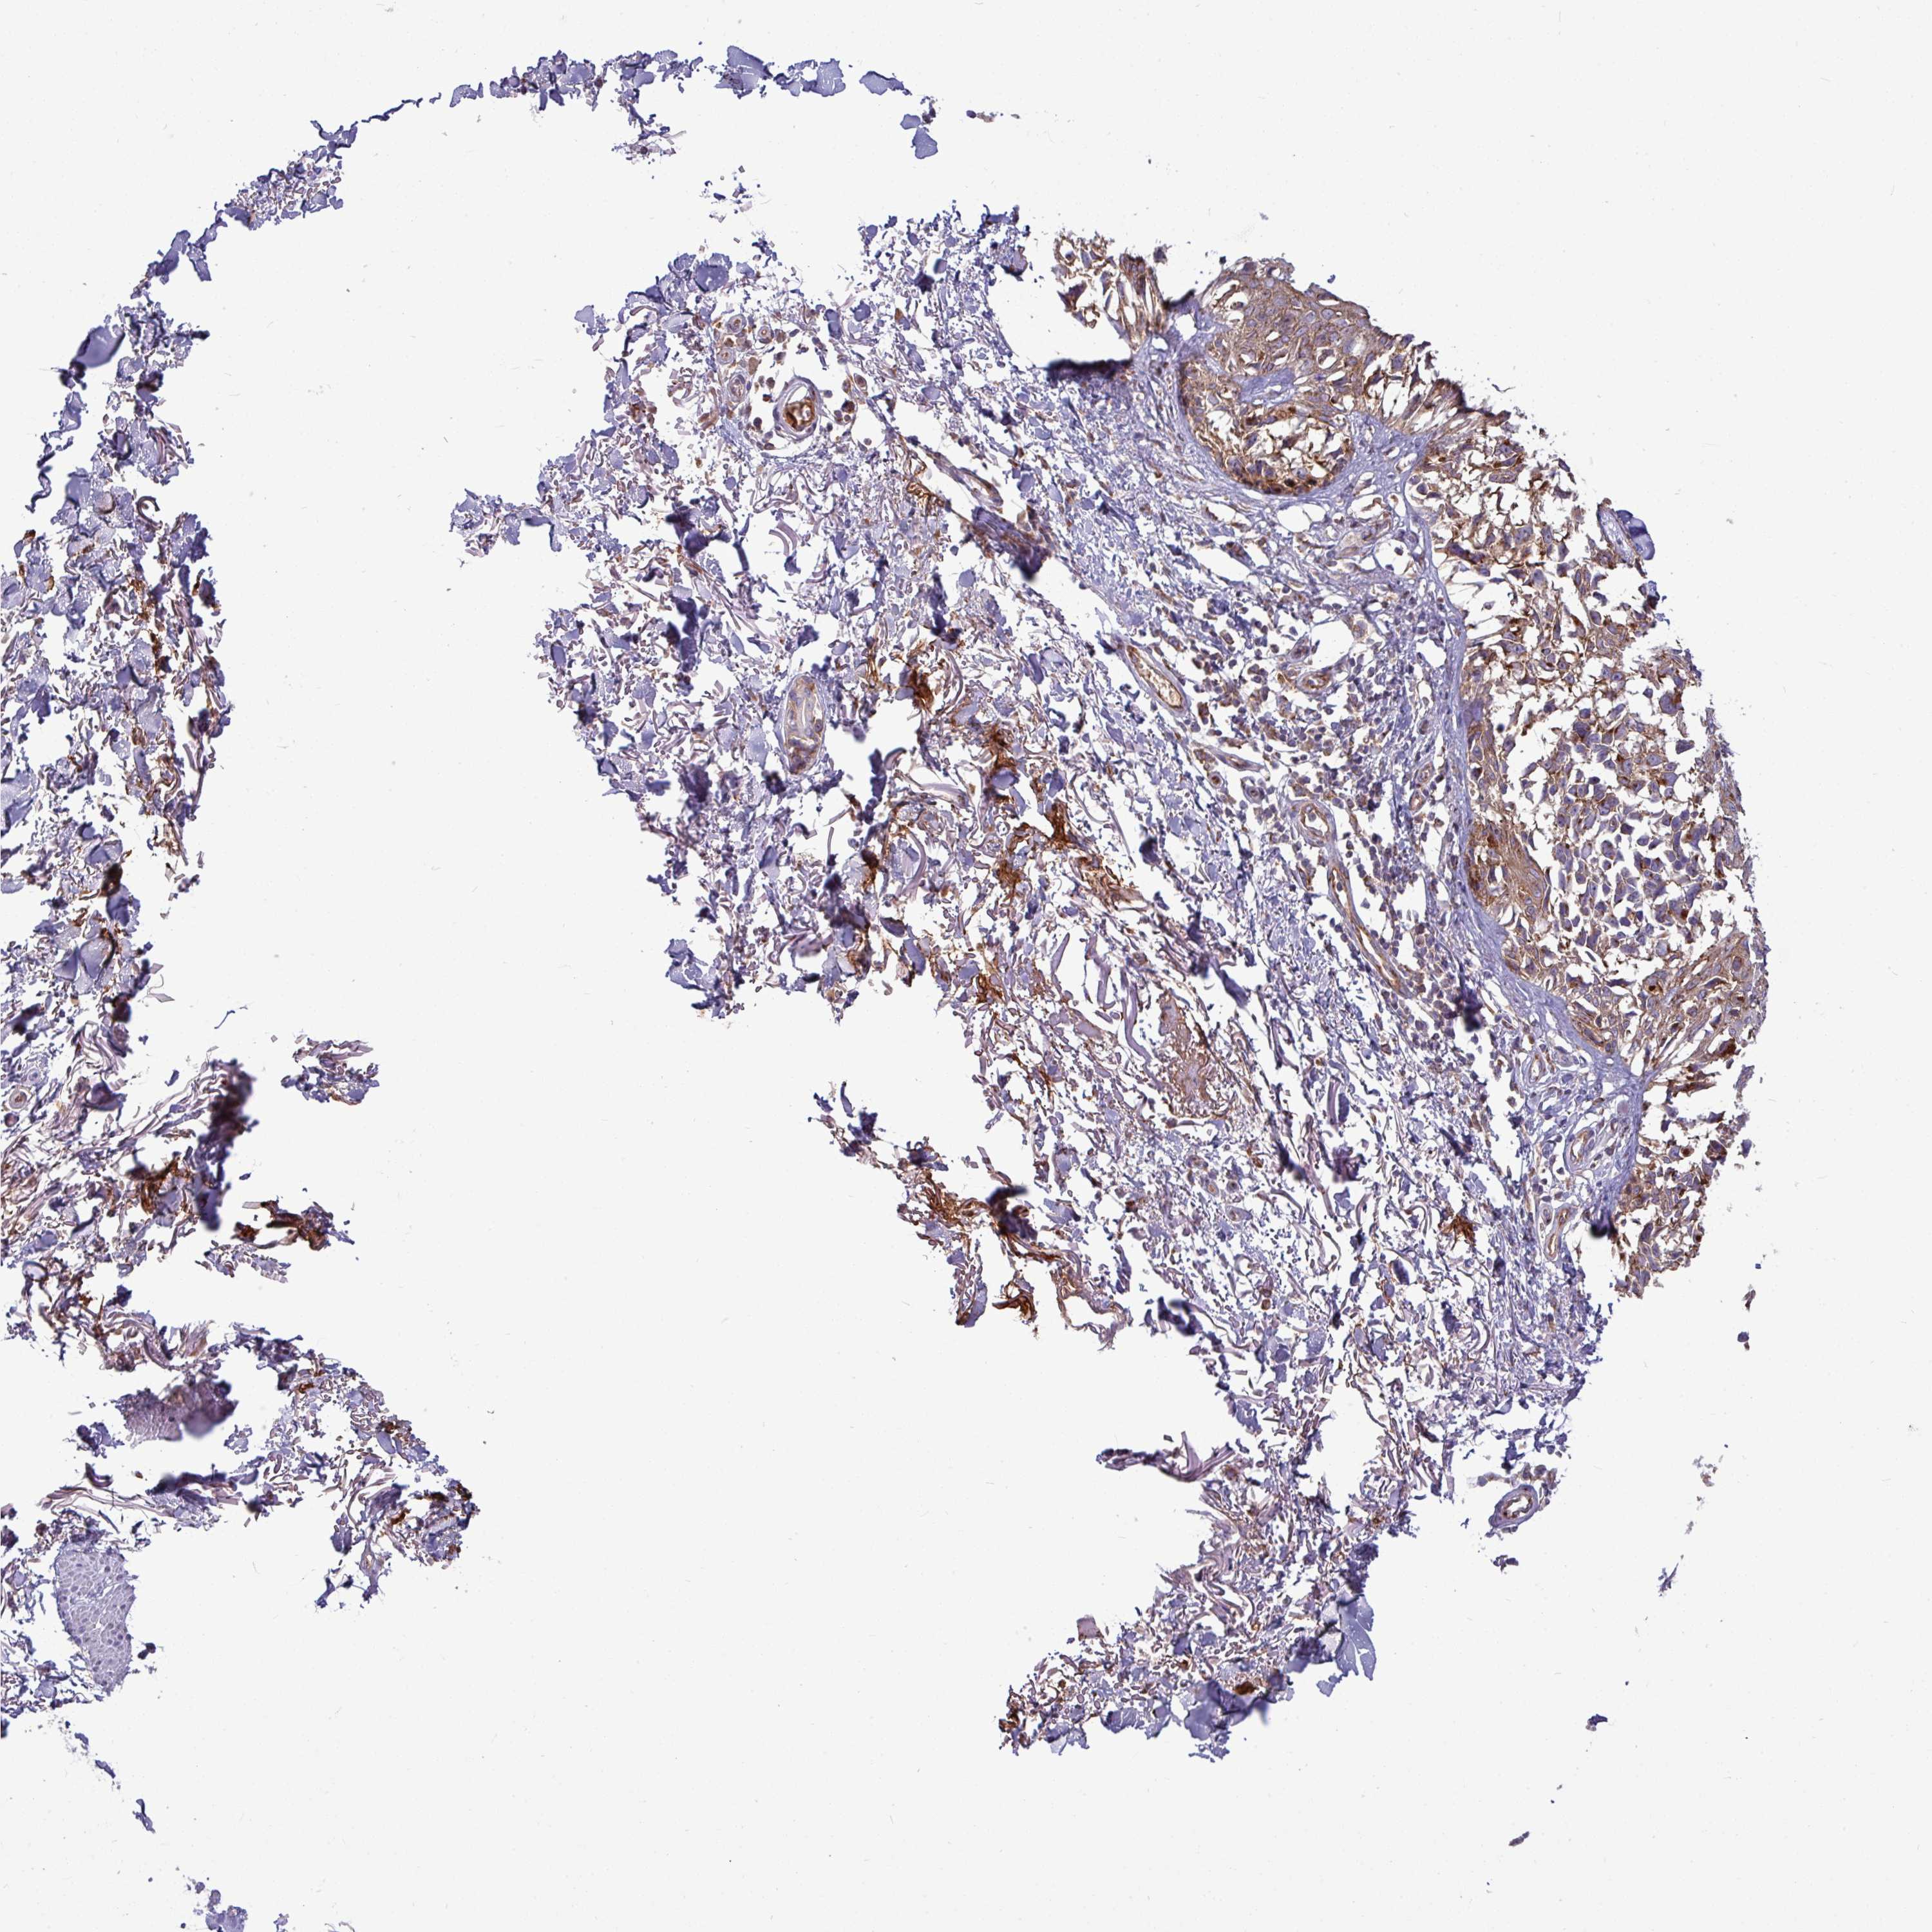

MELANOMA - Protein expressioni

A mouse-over function shows sample information and annotation data. Click on an image to view it in a full screen mode. Samples can be filtered based on level of antibody staining by selecting one or several of the following categories: high, medium, low and not detected. The assay and annotation is described here.

Note that samples used for immunohistochemistry by the Human Protein Atlas do not correspond to samples in the TCGA dataset.

Antibody stainingi

Antibody staining in the annotated cell types in the current human tissue is reported as not detected, low, medium, or high, based on conventional immunohistochemistry profiling in selected tissues. This score is based on the combination of the staining intensity and fraction of stained cells.

Each image is clickable and will lead to virtual microscopy that enables deeper exploration of all samples and also displays staining intensity scores, fraction scores and subcellular localization as well as patient and tissue information for each sample.

Antibody HPA051934

Staining

High

Medium

Low

Not detected

Intensity

Strong

Moderate

Weak

Negative

Quantity

>75%

75%-25%

<25%

None

Location

Nuclear

Cytoplasmic/membranous

Cytoplasmic/membranous,nuclear

Malignant melanoma, NOS